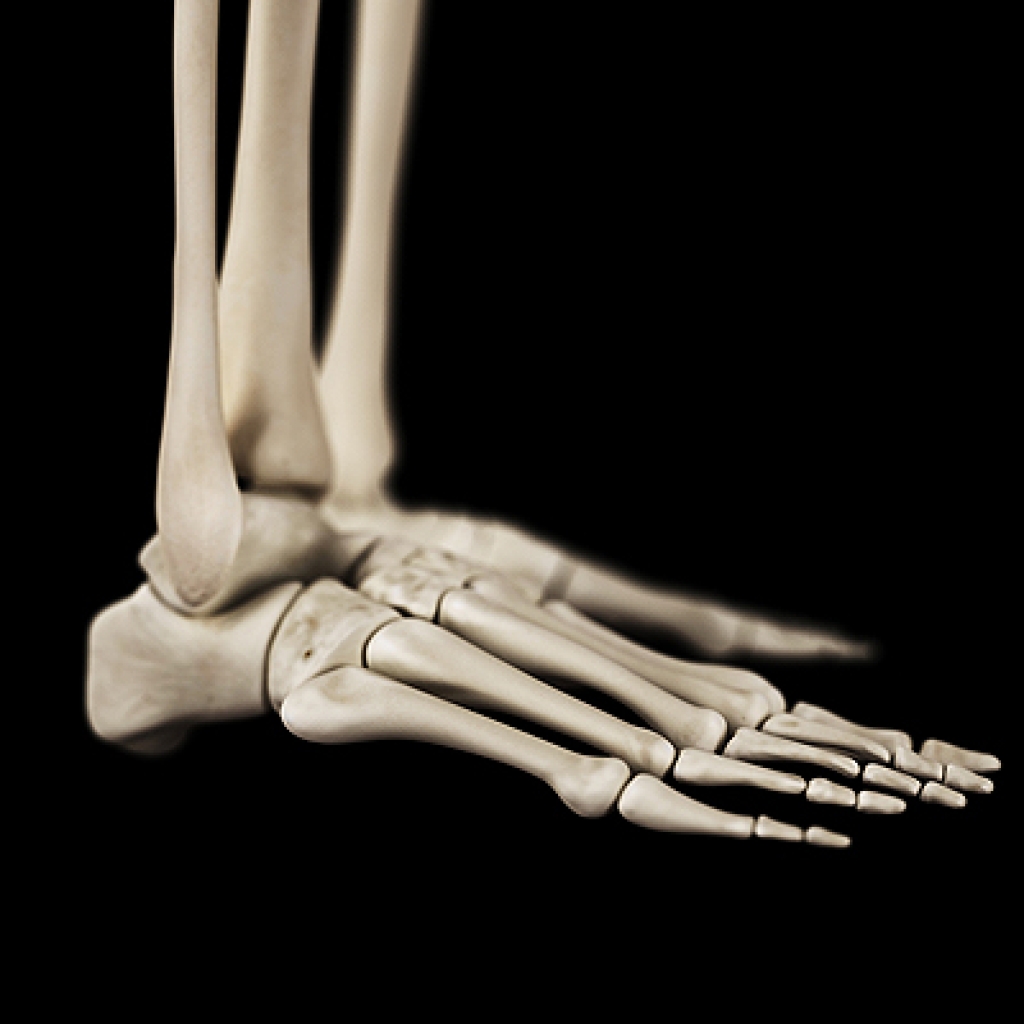

The sesamoid bones act like a pulley that enables the big toe to move normally. The sesamoids also absorb the weight placed on the ball of the foot. Turf toe occurs when the soft tissue surrounding the big toe is injured, which can cause sharp pain. Sesamoiditis is caused from pressure often resulting from inflammation of the sesamoid bones. This inflammation often occurs from overuse in athletic activities. People with high arches may be prone to developing sesamoiditis, as are frequent wearers of high heels. It is recommended to see a podiatrist for sesamoiditis, as they can properly diagnose and treat it.